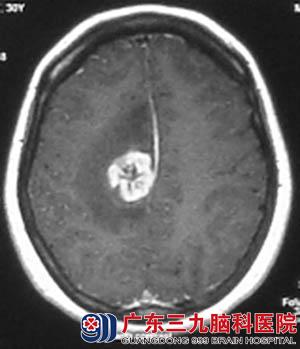

▲2009-10我院就诊前

2008年,冯女士因发作性头晕到当地医院就诊,经检查发现右顶叶病变,未予处理,头晕症状自行缓解。2009年1月复查头颅MR示病变无明显变化,未予治疗。2009年3月患者夜晚再次出现发作性头晕,继而意识不清,口吐白沫,双眼上翻,维持10分钟后症状缓解,半小时后意识恢复,对发作情形不能回忆,未予重视。当年5月再发作一次,症状同前,6月行伽马刀治疗,10月再次出现头晕症状。未进一步治疗转至广东三九脑科医院。

复查MR示病变范围增大,病变周围水肿明显,遂于11月23日在全麻下行“右顶叶深部病变切除术”,病理回报:(右顶叶)星形细胞瘤,WHOⅡ级。